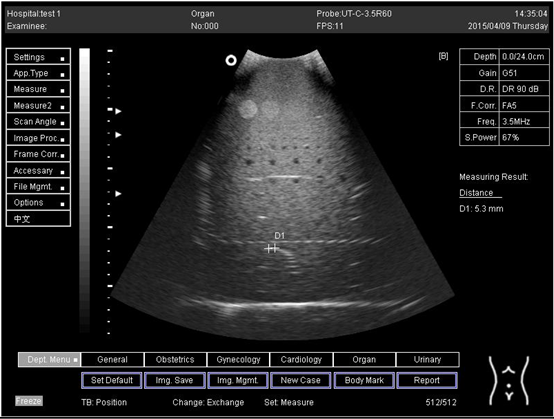

18.0Lateral resolution

Biomimetics 07 00130 i020

D1 = 5.0

D2 = 4.1